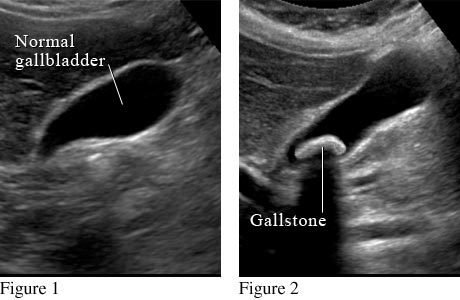

Ultrasound Scan

- Uses high frequency sound waves to create images from inside the body

- Sound waves travel through soft tissue and fluids but bounce off of denser tissue

- The returning sound waves (echo) are measured and used to produce a picture

- Does not use radiation--preferred method for pregnant women

- Often used for imaging internal organs found in the abdomen (ex. gallbladder, liver)